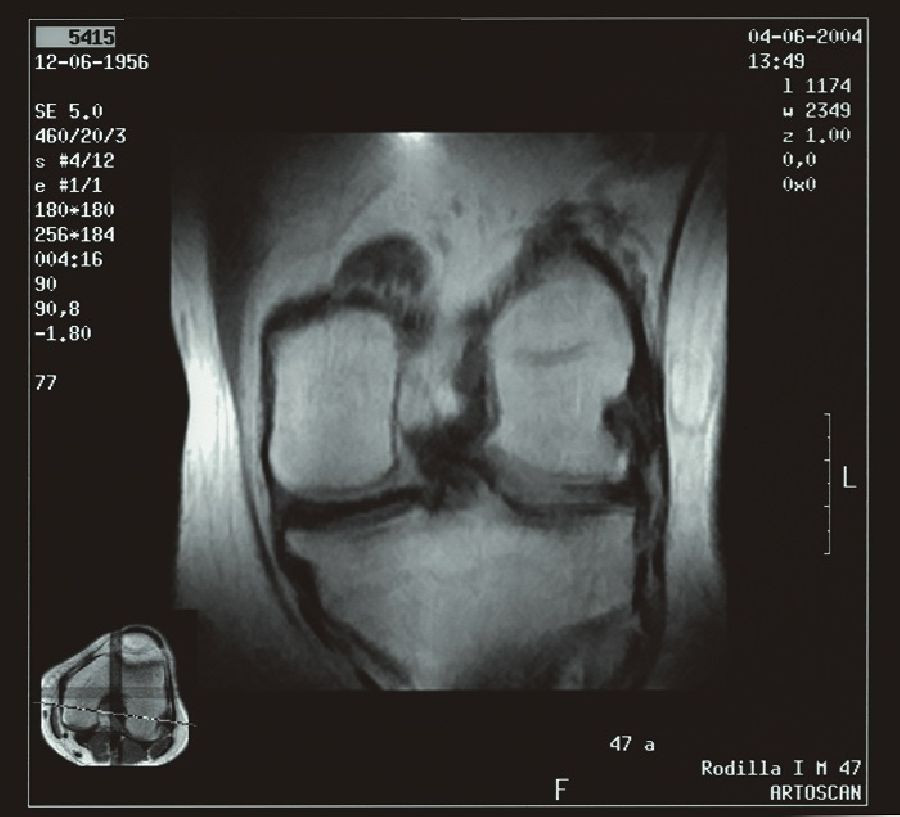

La embolización de la arteria genicular (EAG) reduce la inflamación de la rodilla para mejorar la función y la calidad de vida de las personas con dolor de rodilla de moderado a intenso. La artrosis es una de las causas más comunes de discapacidad, lo que limita las actividades diarias del 40% de todos los adultos estadounidenses.

Hasta hace poco, el dolor de la artrosis se consideraba una enfermedad de \'desgaste y rotura\', pero a medida que el cartílago se descompone libera enzimas que pueden causar inflamación y dolor y limitar el funcionamiento. Este tratamiento reduce el flujo sanguíneo anormal para reducir la inflamación. Si bien mejora rápidamente el dolor de los pacientes, aún más importante es que el alivio del dolor es duradero, con una duración de al menos 12 meses.

Los radiólogos intervencionistas pasaron un catéter a través de una incisión estenopeica en la cadera hasta las arterias de la rodilla artrósica. Luego inyectaron pequeñas partículas para controlar el suministro de sangre a las áreas inflamadas y dolorosas de la rodilla.